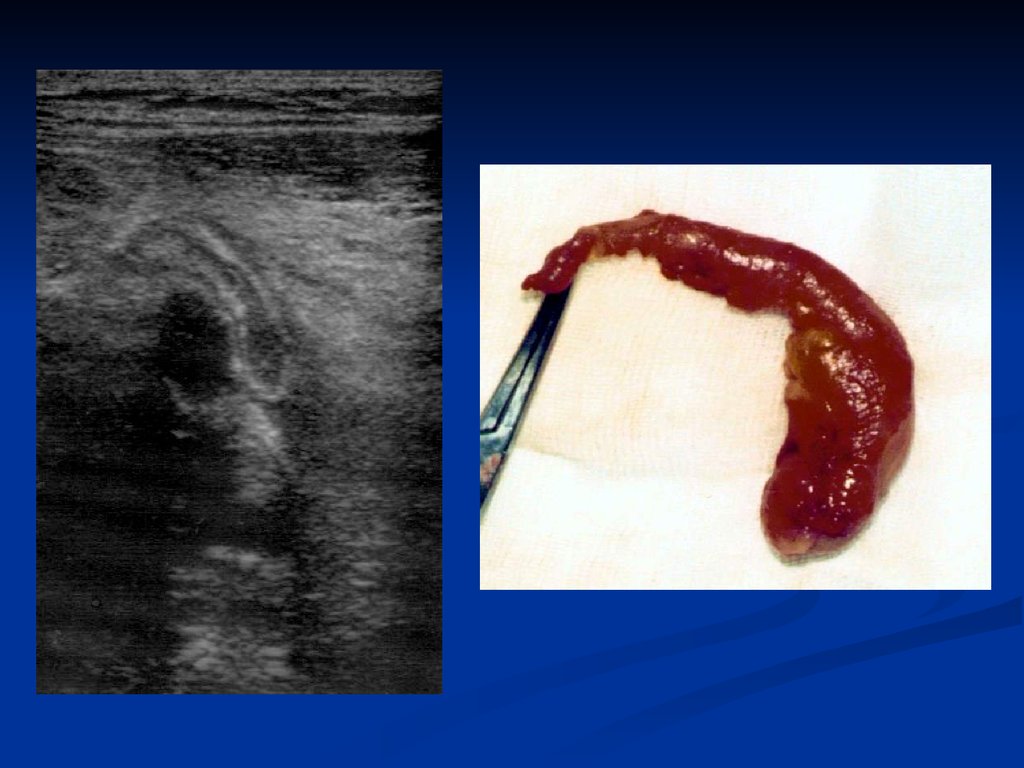

Последние годы

хорошим подспорьем в

диагностике острого аппендицита является

ультразвуковое

исследование.

Если

неизмененный червеобразный отросток

увидеть сложно, то воспаленный, то есть с

утолщенной

стенкой

и

растянутый

содержимым,

аппендикс

может

быть

обнаружен в большинстве случаев. На Рис.4

видно,

как

ультразвуковой

имидж

15.